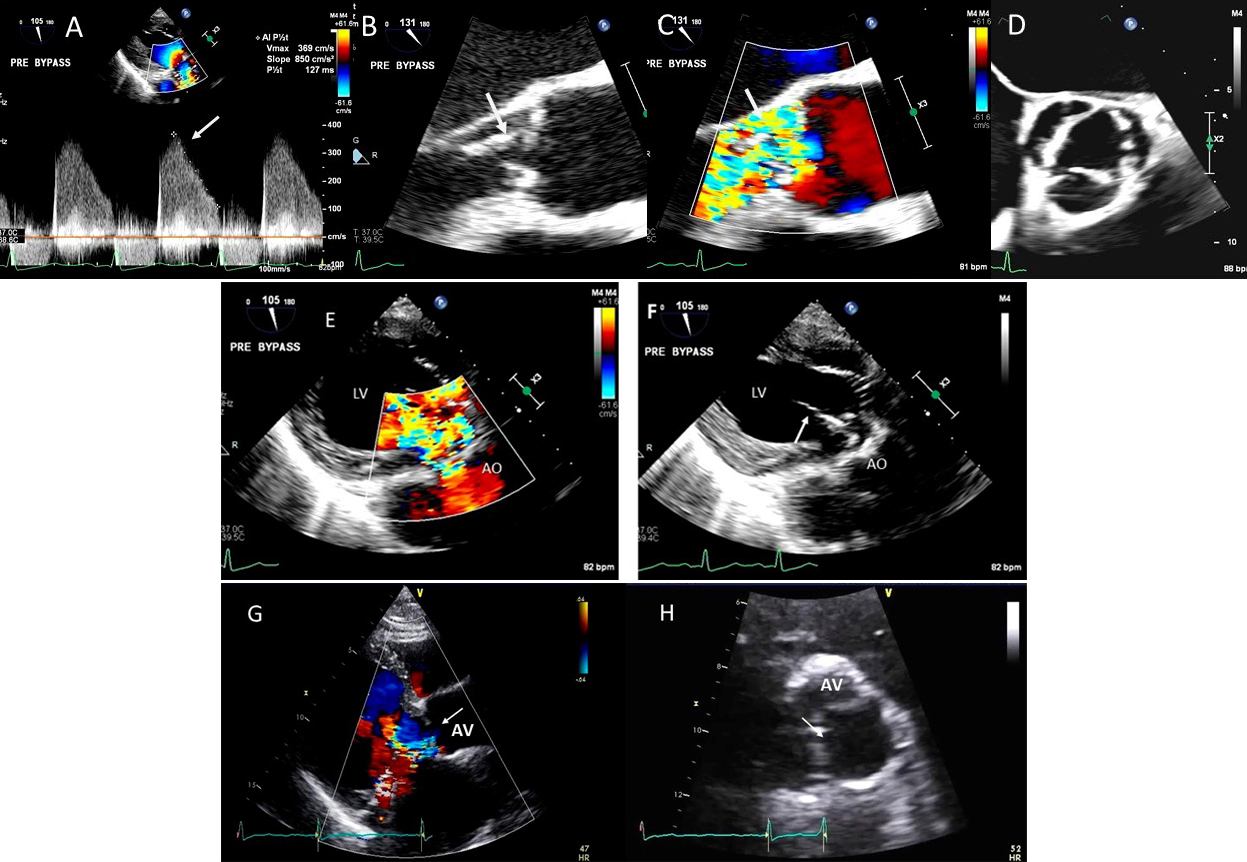

These criteria are generally more reliable in central jets. Pulmonary artery systolic pressure, mitral inflow E wave velocity and pulmonary vein flow pattern are other helpful parameters. Systolic pulmonary vein reversal (Fig. 1) is highly specific for severe MR but is not very sensitive. Discrepancy may occur between MR ERO and RV in mitral valve prolapse in early stages of MR where non holosystolic MR jet duration and hence regurgitant volume are smaller than the PISA derived EROA which does not account for the duration of MR jet. 2D vena contracta width may be unreliable in eccentric jets, however direct measurement of regurgitant orifice can be done using 3D color Doppler vena contracta area which may allow better quantitation of MR in central as well as eccentric MR jets [5] as well as in patients with multiple MR jets in whom PISA quantitation by adding multiple jets has not be validated and in whom continuity equation cannot be performed [6].

Fig. 1.Degenerative MR due to Flail posterior mitral valve leaflet. (A) TEE 4 chamber view showing a flail posterior mitral valve resulting in a severe anteriorly directed mitral regurgitation jet. LA, left atrium; LV, left ventricle; AML, anterior mitral leaflet; PML, posterior mitral leaflet. (B) TEE 4 chamber view color Doppler showing anteriorly directed mitral regurgitation with PISA (red arrow). AML, anterior mitral leaflet; AV, aortic valve. (C) Pulsed wave Doppler showing left upper pulmonary vein systolic flow reversal. (D) 3D TEE enface view of the mitral valve from the atrial perspective demonstrating P2 flail scallop with torn chordae. Aortic valve is a 9 o’clock position. AML, anterior mitral leaflet; PML, posterior mitral leaflet.